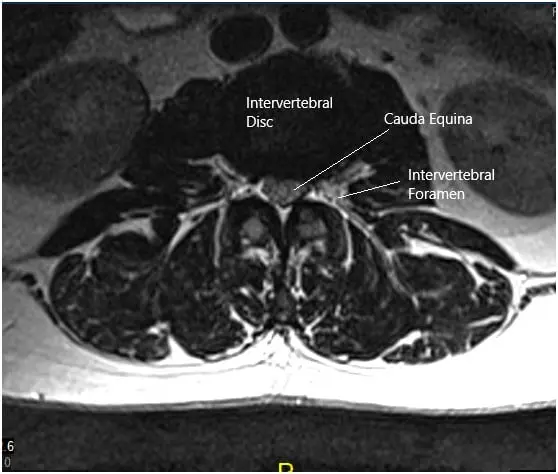

A 50-year-old male patient who started experiencing excruciating pain down his left leg with weakness in that leg and numbness in his peroneal region.  His sensory deficit included his lateral thigh and entire foot as well. He obtained an MRI that showed a disk fragment compressing on the L5 and S1 nerve roots with severe lumbar stenosis in the lateral recess and encroachment on the left side at L5 and S1.

Grade I anterolisthesis of L2 on L3. Straightening of the lumbar lordosis. Degenerative changes are identified diffusely within the lumbar spine. At L5-S1, there is a left-sided disc herniation/protrusion causing mild narrowing of the thecal sac and narrowing of the left lateral recess. This encroaches upon the left S1 nerve root within the left lateral recess.

The hernia also extends into the proximal left neural foramen causing mild narrowing. The mild right neural foraminal narrowing is also visualized. Mild to moderate narrowing of the thecal sac is identified at L2-3.

MRI of the lumbosacral spine in sagittal and axial views 2

MRI of the lumbosacral spine in sagittal and axial views.